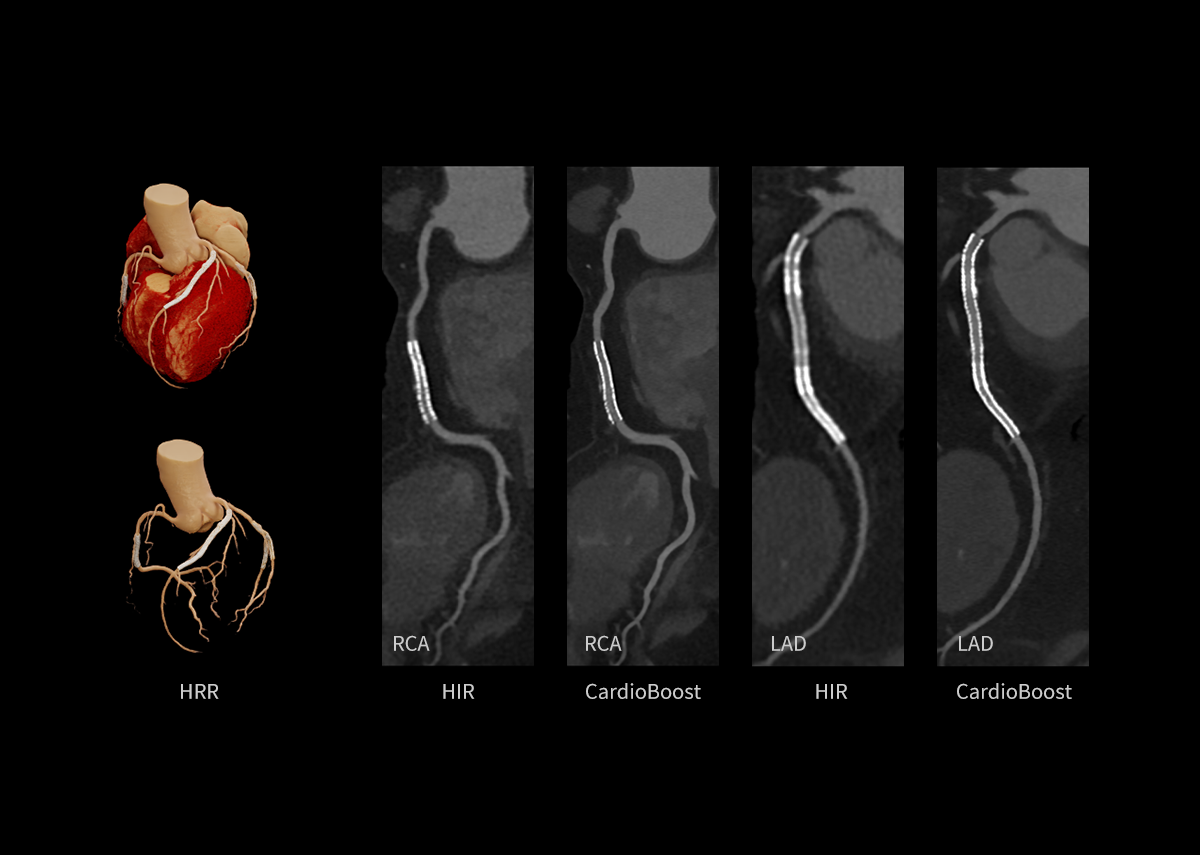

Throughout the iterative loop of forward and backward projection between the raw data domain and the image domain, AIIR consistently takes into account the accurate modeling of optics, noise, anatomy, and physics statistics. Additionally, AIIR integrates deep learning-based de-noising technology, supplanting the conventional regularization role of MBIR in the optimization reconstruction process.

In brief, AIIR utilizes deep learning-based AI technology to attain robust noise reduction and natural image texture, while incorporating MBIR technology to achieve precise anatomical structure representation and artifact suppression. This technique surpasses the limitations of using either MBIR or deep learning reconstruction (DLR) independently.